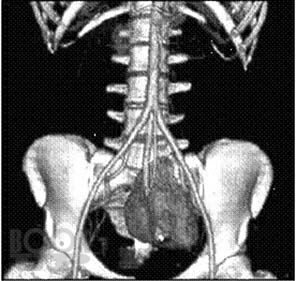

Аномалии развития почек: диагностика и лечение

Изложены вопросы этиологии, патогенеза, классификации, диагностики и лечения аномалий развития почки. Отдельным разделом представлены сведения о кистозных образованиях почки, как наиболее частых заболеваниях почечной структуры, имеющих тенденцию к злокачественному перерождению и требующих дифференциальной диагностики с онкологическими процессами в почке. Детально освещены диагностика и современные малоинвазивные методы лечения простых кист.